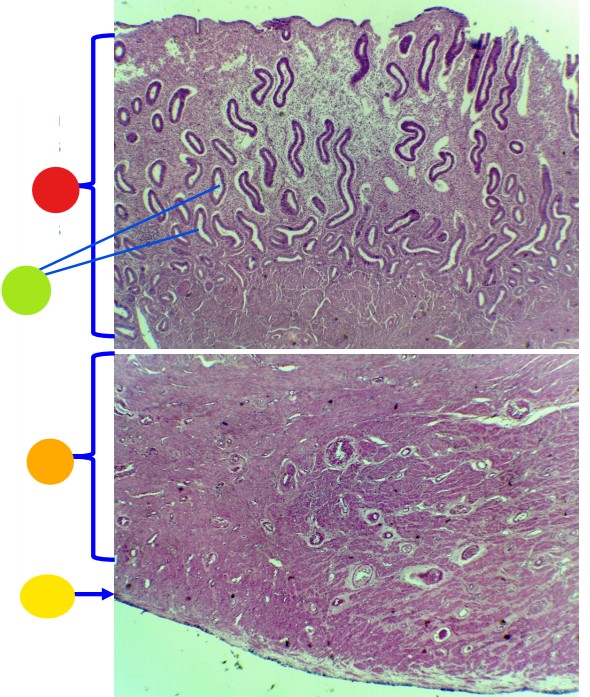

red

tunica albuginea

orange

primordial follicles

red

primary follicle

orange

secondary follicles

what is this

tertiary follicle